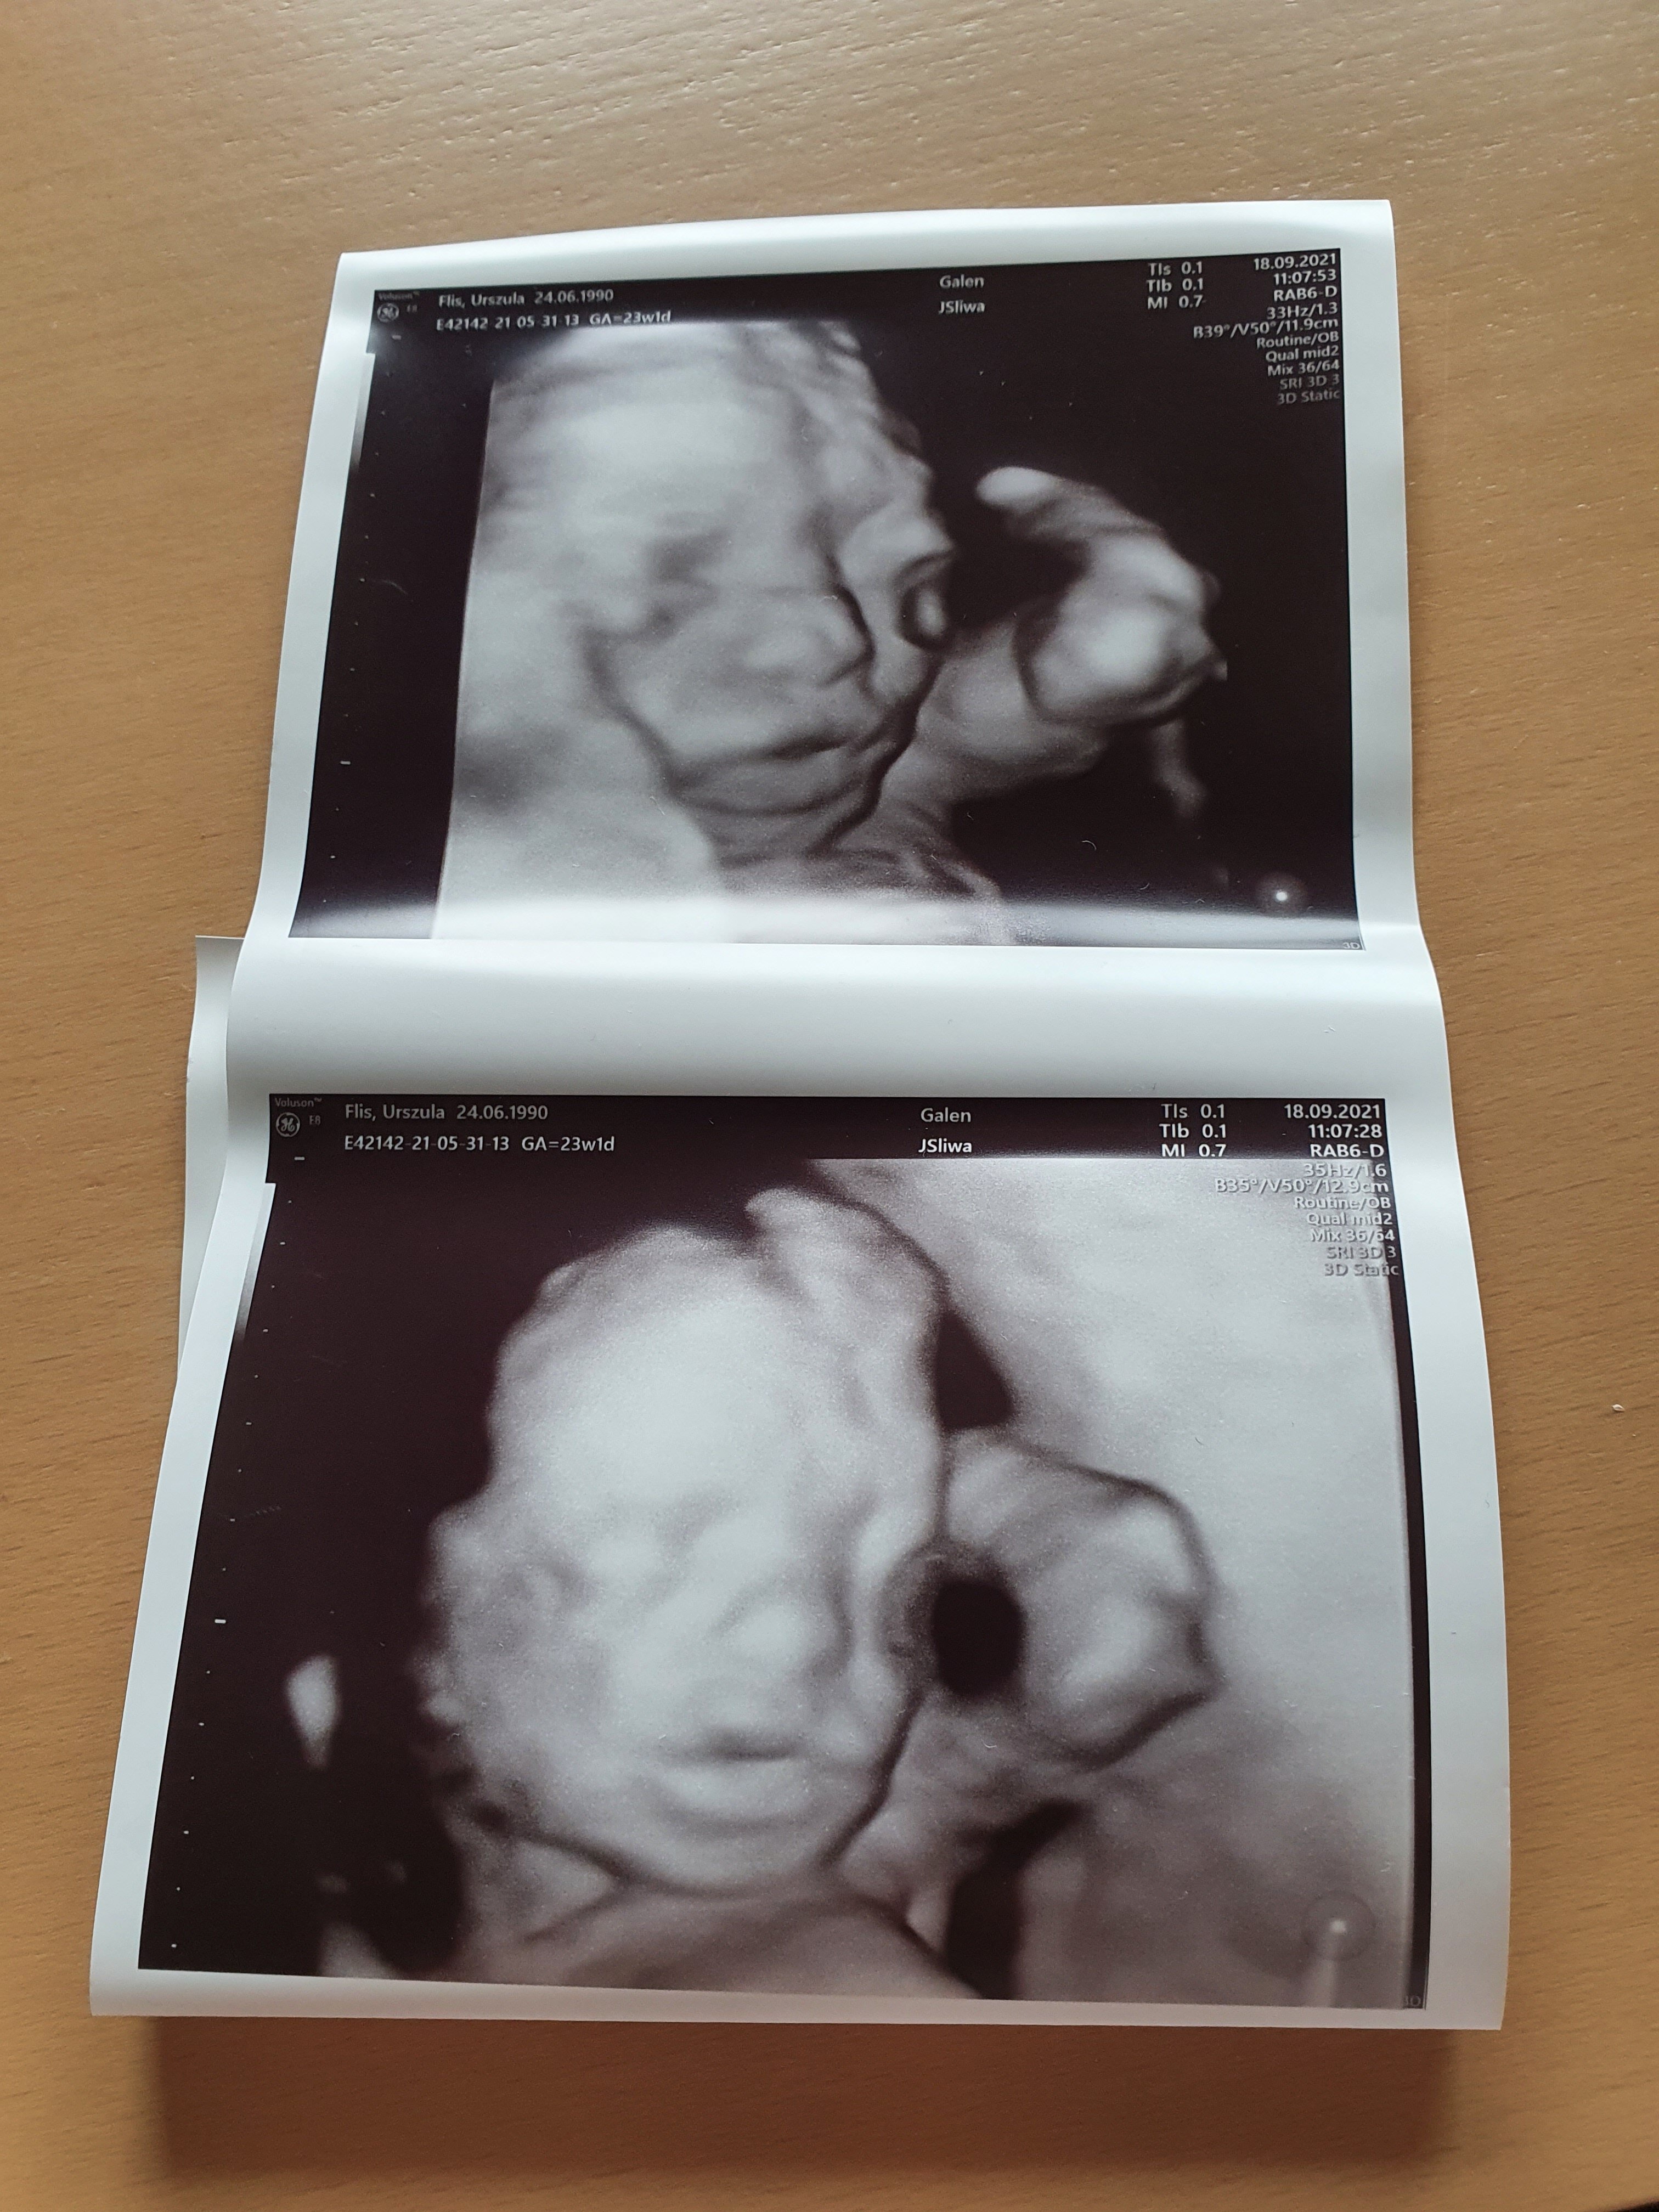

Dzisiaj mialam połówkowe i nasz maly nie będzie taki maly;) ale na szczęście będę miała cesarkę wiec dam rade;) i z tego wszystkiego lekarza nie spytałam co mam wziąć na to chyba przeziebienie🙈

A dwa dni temu mieliśmy też połówkowe :) Mała waży już prawie 0,5kg i rozwija się zdrowo 😍

Śliczne zdjęcia! Będzie pamiątka [emoji4]

Dzisiaj mialam połówkowe i nasz maly nie będzie taki maly;) ale na szczęście będę miała cesarkę wiec dam rade;) i z tego wszystkiego lekarza nie spytałam co mam wziąć na to chyba przeziebienie[emoji85]